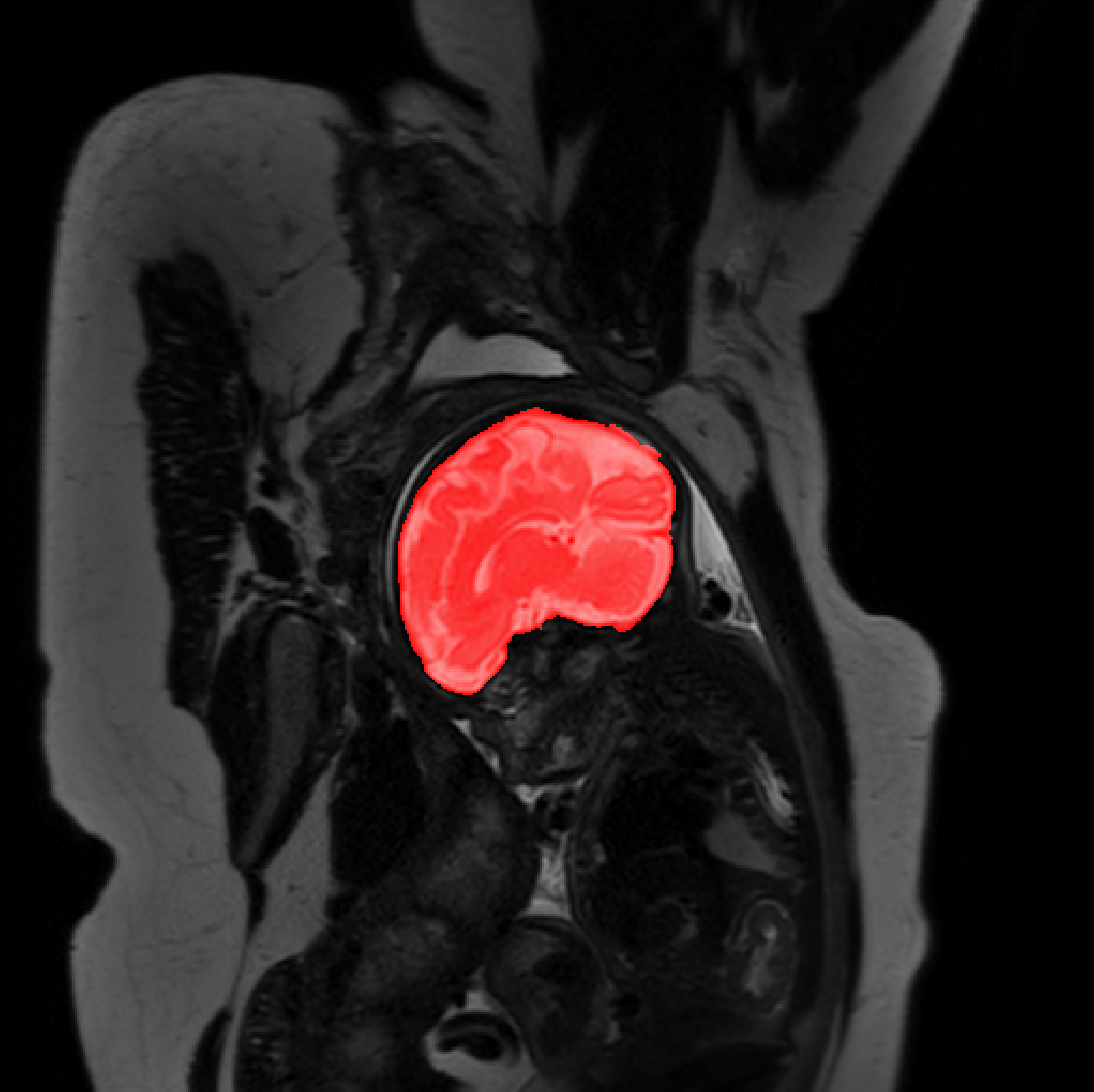

Refer to caption

Figure 3: Example of ICV segmentations in images acquired in axial (left), coronal (middle) and sagittal (right) planes. Top row: A slice from T2-weigted image; Second row: Automatic segmentations obtained using 7 training images from the representative imaging planes; Third row: Automatic segmentations obtained using all 21 training images from all 3 image orientations; Bottom row: Manual segmentation.